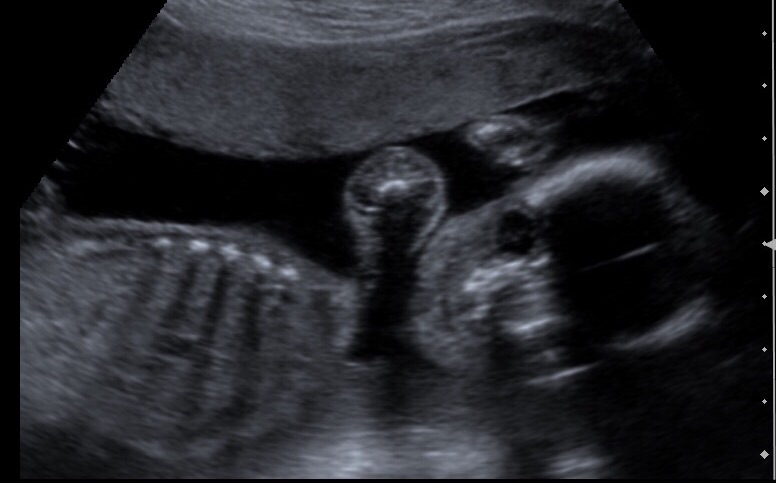

The baby is much cuter than seeing me right now. I fall more in love when I see him. Did my fetal Echo and advanced a/s and things are looking good for him